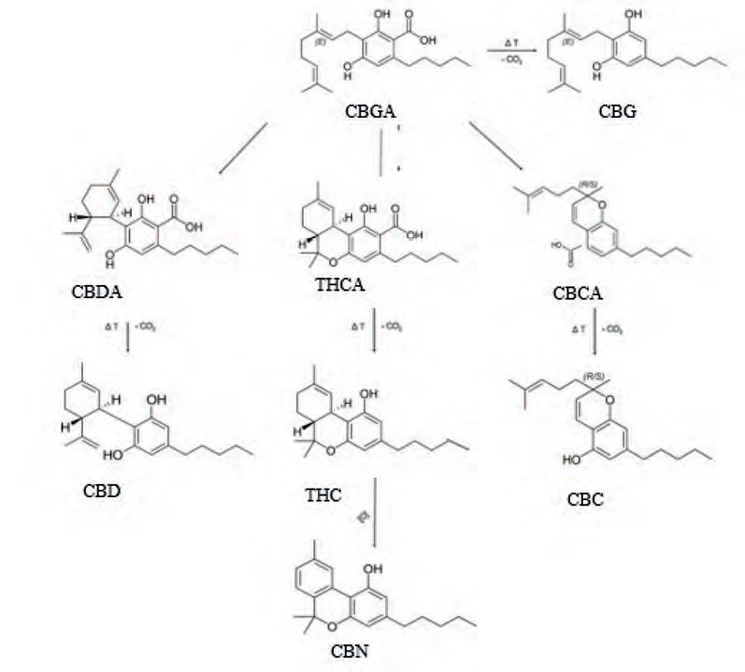

Kanabinoidní kyseliny jsou prekurzory neutrálních kanabinoidů. Dekarboxylací kanabinoidních kyselin působením světla a tepla vznikají neutrální kanabinoidy (11).

Biosyntéza (Obr. 5) začíná vytvořením dvou kanabinoidních prekurzorů – geranyldifosfátu a olivetové kyseliny, které spolu kondenzují za účasti geranyltransferasy a vzniku kanabigerolové kyseliny (CBGA). CBGA se následně transformuje na tetrahydrokanabinolovou kyselinu (THCA), kanabidiolovou kyselinu (CBDA) a kanabichromenovou kyselinu (CBCA) pomocí THCA synthasy, CBDA synthasy a CBCA synthasy. Tetrahydrokanabinol (THC), kanabidiol (CBD), kanabigerol (CBG) a kanabichromen (CBC) vznikají dekarboxylací ze svých kyselin během skladování vlivem tepla a světla za uvolnění CO211. THC a iso-THC mohou také vznikat kysele katalyzovanou cyklizací CBD vytvořením příslušných karbokationtů na C-8 a C-1 CBD skeletu (25).

PČR: Obr. 5 – Biosyntéza kanabinoidů a hlavní rozkladné produkty THC (8)

PČR: Obr. 5 – Biosyntéza kanabinoidů a hlavní rozkladné produkty THC (8)